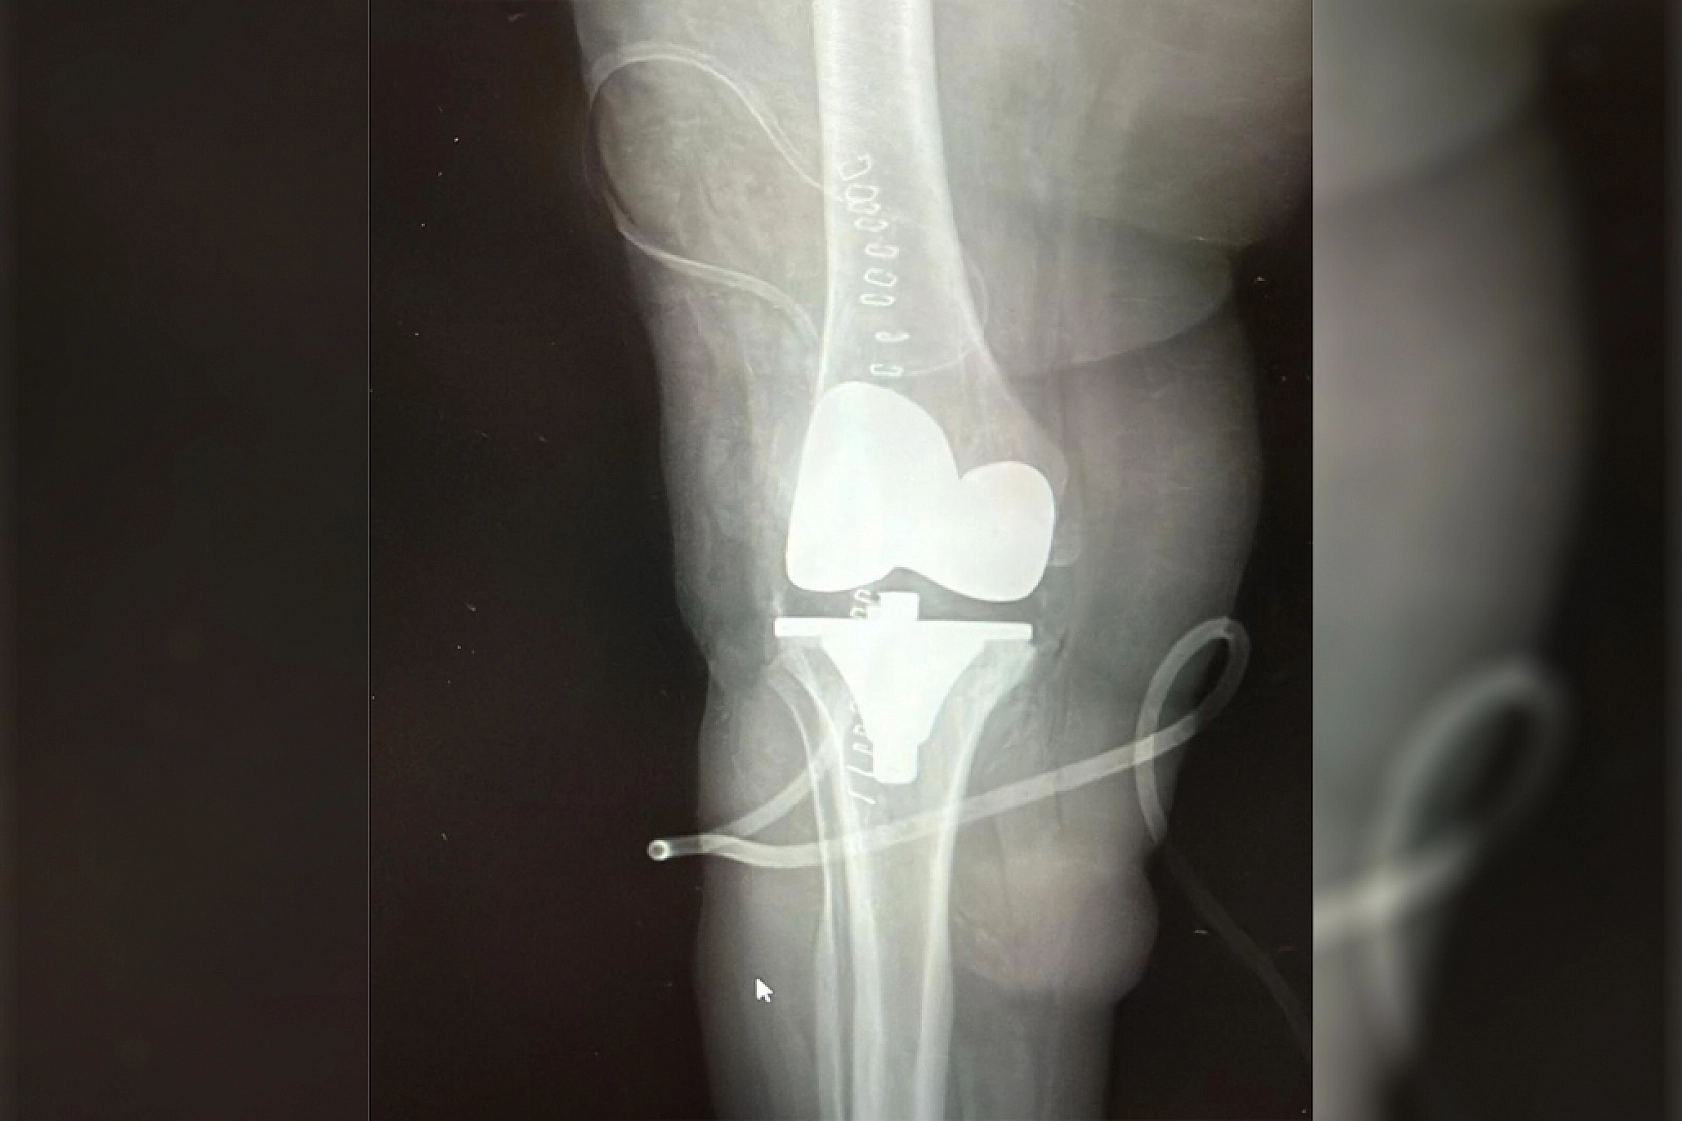

Malatya'da diz ağrısı ve hareket kısıtlılığı şikayetiyle hastaneye başvuran 73 yaşındaki Elif Büyükbirer'in dizinden, yapılan ameliyatta 24 adet taşlaşmış tümör çıkarıldı.